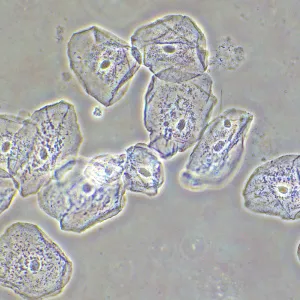

Фазово-контрастное устройство MAGUS SPH2 – это набор аксессуаров, которые позволяют реализовать на микроскопе MAGUS метод фазово-контрастной микроскопии. Фазовый контраст применяют для изучения прозрачных объектов, слабо различимых в светлом поле. Этот метод не требует окрашивания, повреждающего структуру живых образцов, поэтому подходит для широкого круга медицинских и фармакологических исследований.

Фазовый объектив имеет существенное конструктивное отличие от штатного объектива микроскопа – в нем присутствует фазовое кольцо, которое находится в плоскости выходного зрачка. В комплект ФКУ включены 4 объектива – с увеличением 10х, 20х, 40х и 100х. Все объективы рассчитаны на бесконечность и являются планахроматами, т. е. обеспечивают высокую степень выравнивания поля зрения (до 90%) и эффективно минимизируют сферические и хроматические искажения. Парфокальная высота объективов – 60 мм.